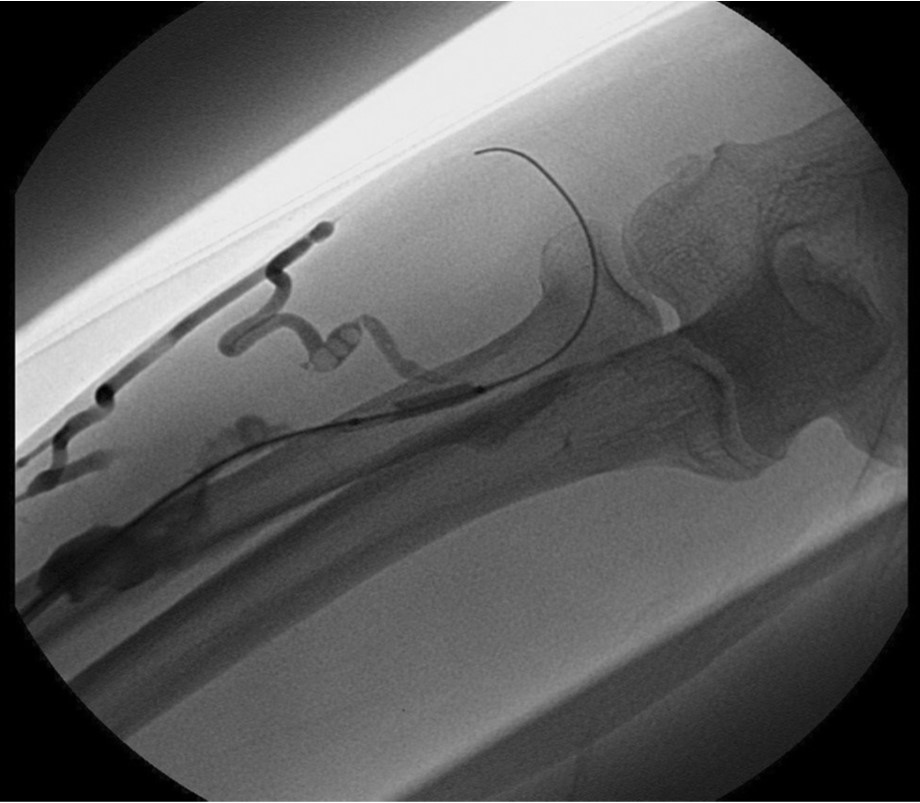

Initial shuntogram 상 total stenotic occlusion된 antecubital vein과 cephalic & basilic veins이 확인되었다(Fig. 1) 투시하에서 더 이상의 outflow vein을 확인할 수 없었으며 초음파상 1mm 크기에 가까운 흔적으로 확인되었다(Fig. 2). 7Fr, 24cm sheath(Accu-Sheath, Sung wonmedical, Korea, Cheongju) 로 폐색된 앞부위까지 전진시킨 후, 투시를 보조수단으로 하며 초음파를 main 유도 기구로 사용하여 real time으로 초음파 probe를 0.035’ J-tip & straight-tip guide wires(Terumo, Tokyo, Japan)와 5 Fr Kumpe catheter(Soft-Vu, AngioDynamics, USA, NY) 바로 위에 위치 시키면서 wire를 전진시켰다(Fig. 3). 시술 중 guide wire 가 혈관 외부로 뚫고 나가며 parenchymal injury를 유발하였다(Fig. 4A, B). 그 후 venous true lumen을 찾 angioplasty를 시행하였다(Fig. 5). 마지막 shuntogram 상 더 이상의 혈관 손상이 없이 재개통된 것을 확인하고 시술을 종료하였다(Fig. 6).

Fig. 1.

AV fistulogram : occlusion of antecubital vein with collateral flows